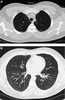

Lung granuloma

A granuloma is an aggregation of macrophages that forms in response to chronic inflammation. This occurs when the immune system attempts to isolate foreign substances which it is unable to eliminate. [Source: Wikipedia ]